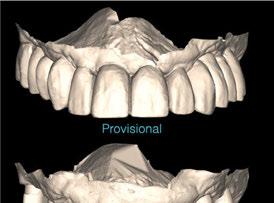

A los 6 meses de cicatrización, se realizó un nuevo CBCT, obteniendo un nuevo archivo DICOM que alineamos con el STL del encerado. De esta manera, se planificó la posición de los implantes a 4 mm del margen de la restauración final y se diseñó y confeccionó la férula de cirugía guiada dentosoportada en 12-13 y 22-23, la cual imprimimos con la impresora 3D Formlabs®. El provisional

de carga inmediata lo diseñamos con el programa de diseño 3D Exocad® a partir del encerado y se imprimió también en clínica con la misma impresora 3D (Figuras 14-16).